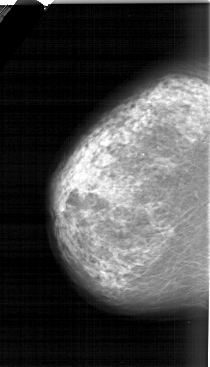

A_1315_1.LEFT_CC

LEFT_CC LINES 6226 PIXELS_PER_LINE 3556 BITS_PER_PIXEL 12 RESOLUTION 43.5 NON_OVERLAY